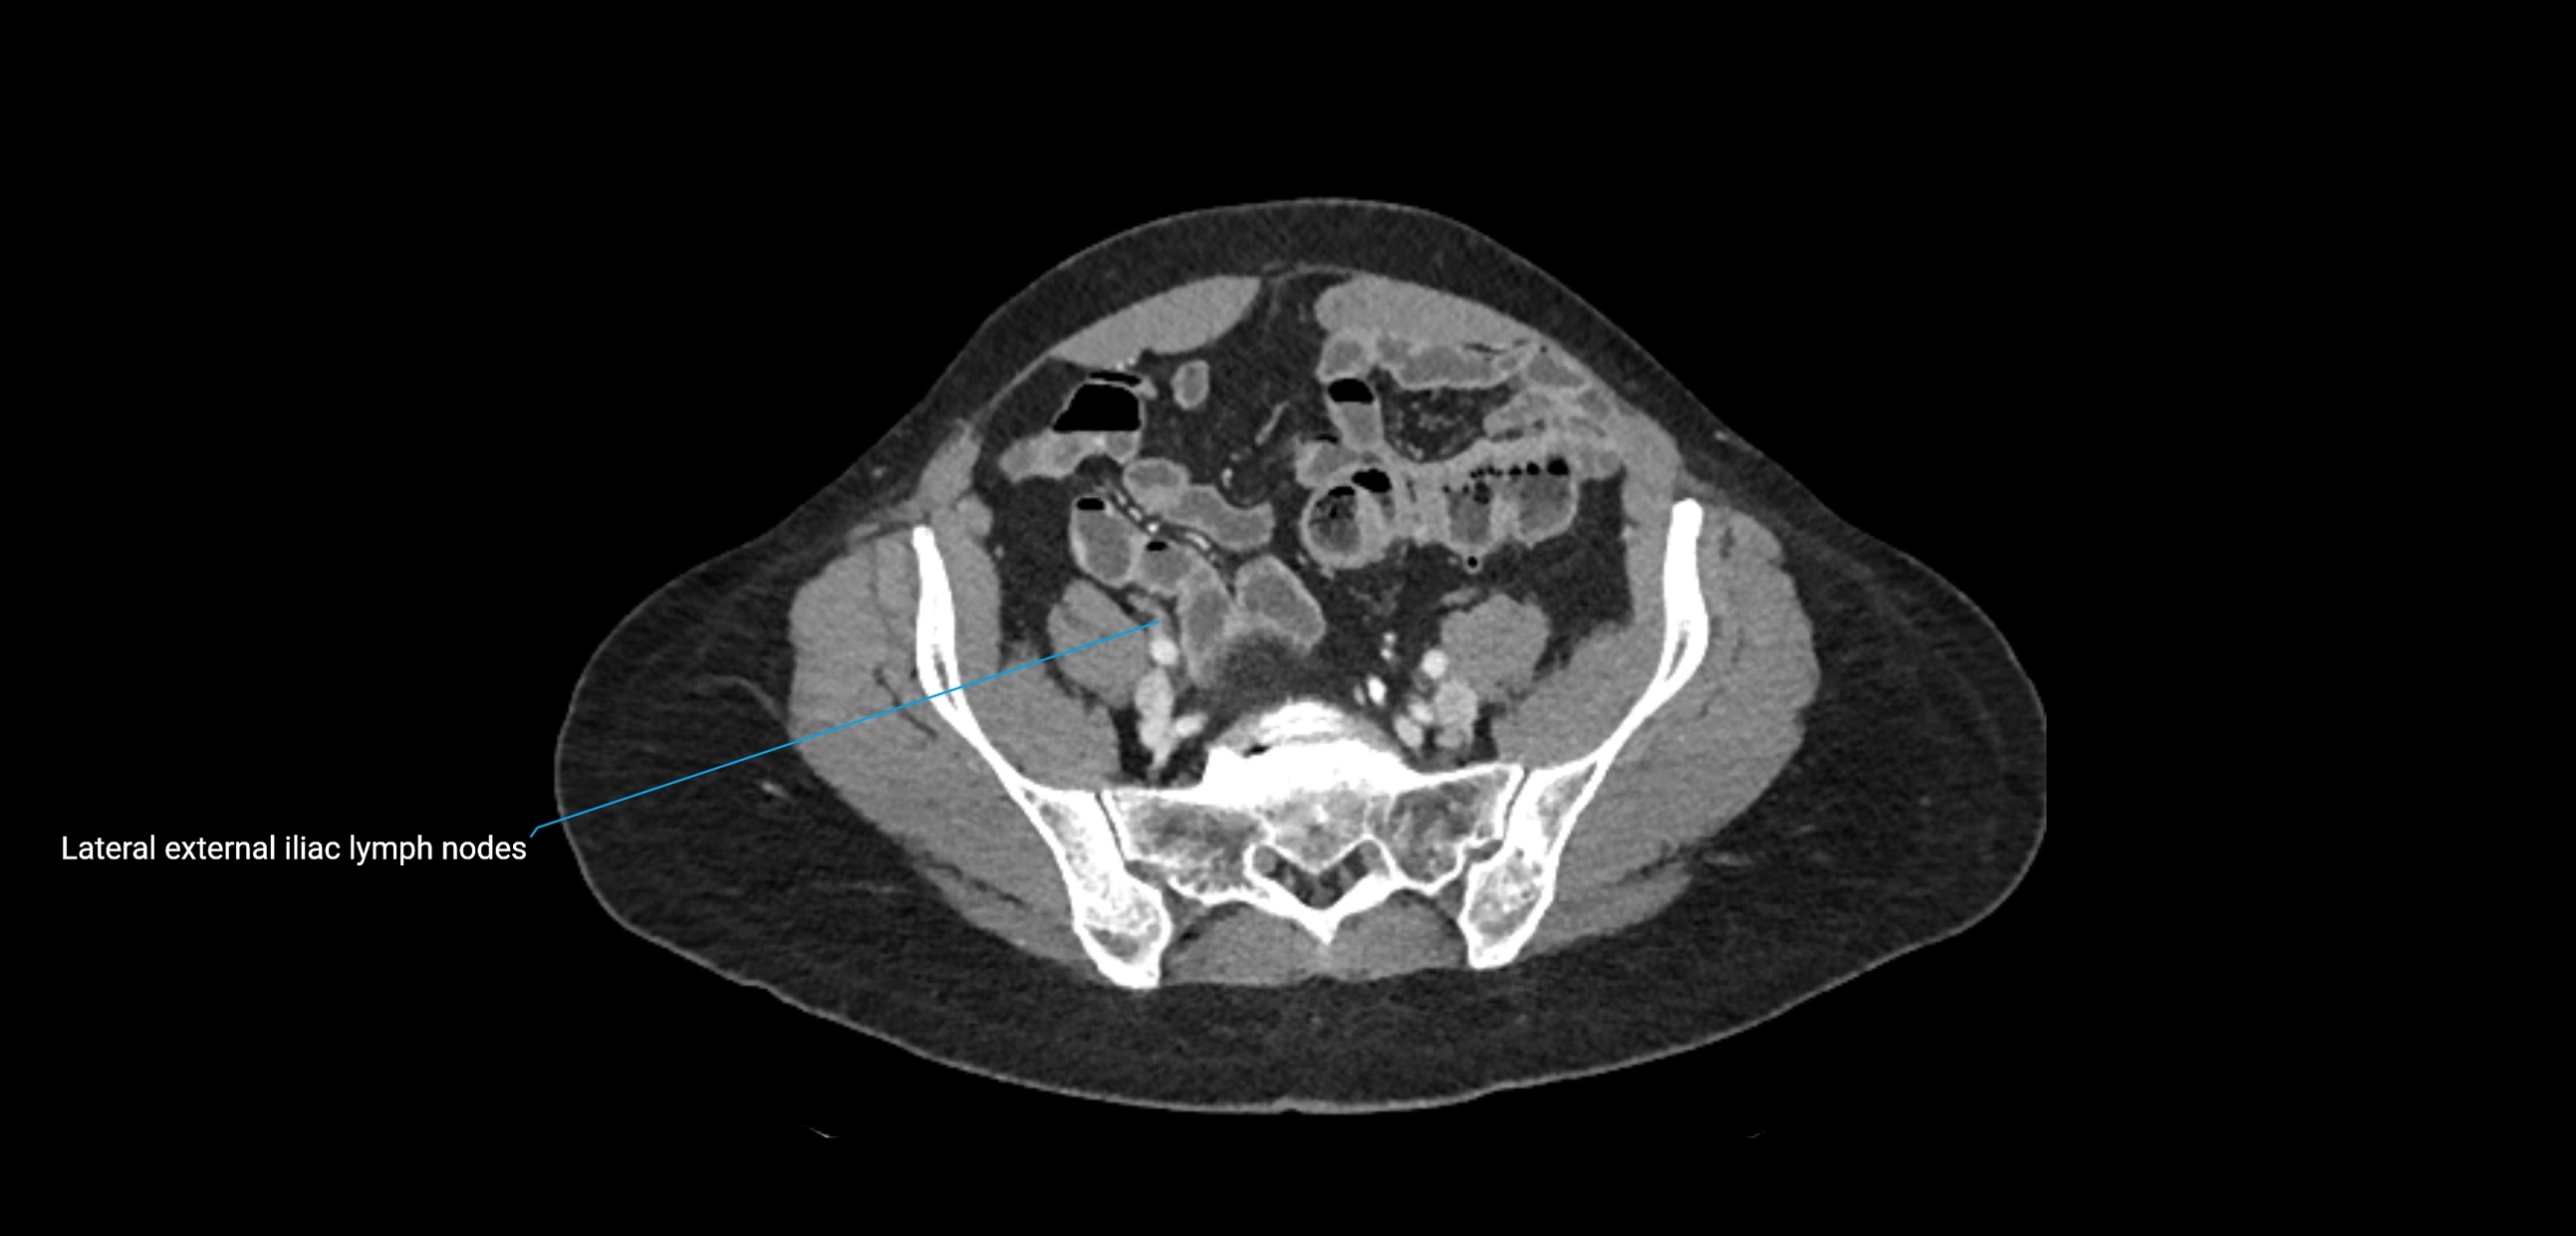

CT image

image